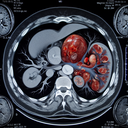

МРТ органів черевної порожнини

Магнітно-резонансна томографія (МРТ) органів черевної порожнини – це неінвазивний метод діагностики, який дозволяє отримати детальні зображення органів і структур всередині живота. Ось кілька ключових моментів: 1. **Навіщо робити МРТ:** - Виявити пухлини, кісти або інші аномалії...